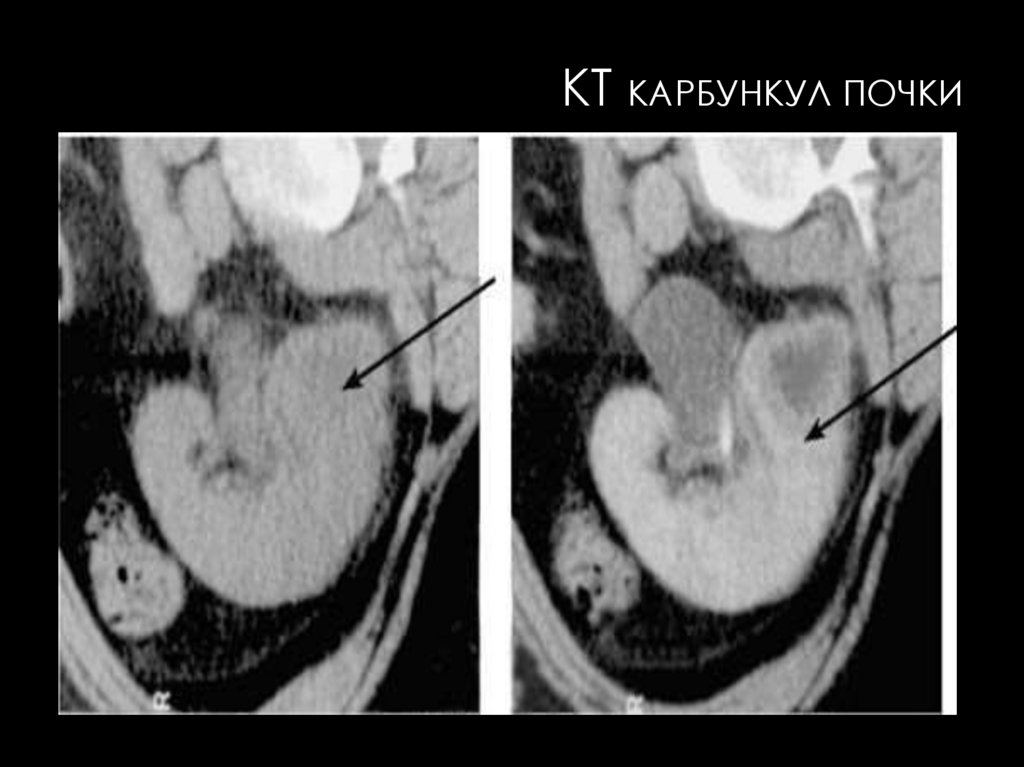

КТ КАРБУНКУЛ ПОЧКИ